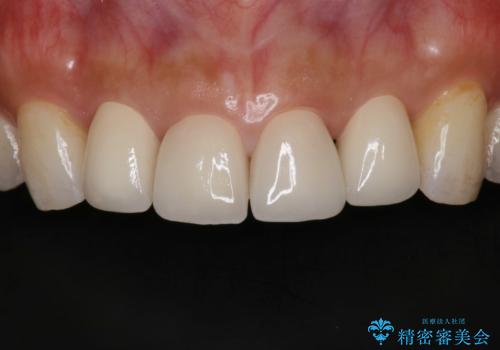

前歯の形気になる セラミッククラウン(SP)

- 矯正終了した患者様で、前歯の形が気になるということで

セラミッククラウンにて治療された方の症例です。

患者様と何度か修正を加えながら歯の形、色に満足していただけました。

また、神経がある歯なのでシミたりすることが場合によってはありますので、担当歯科医師にご相談ください。